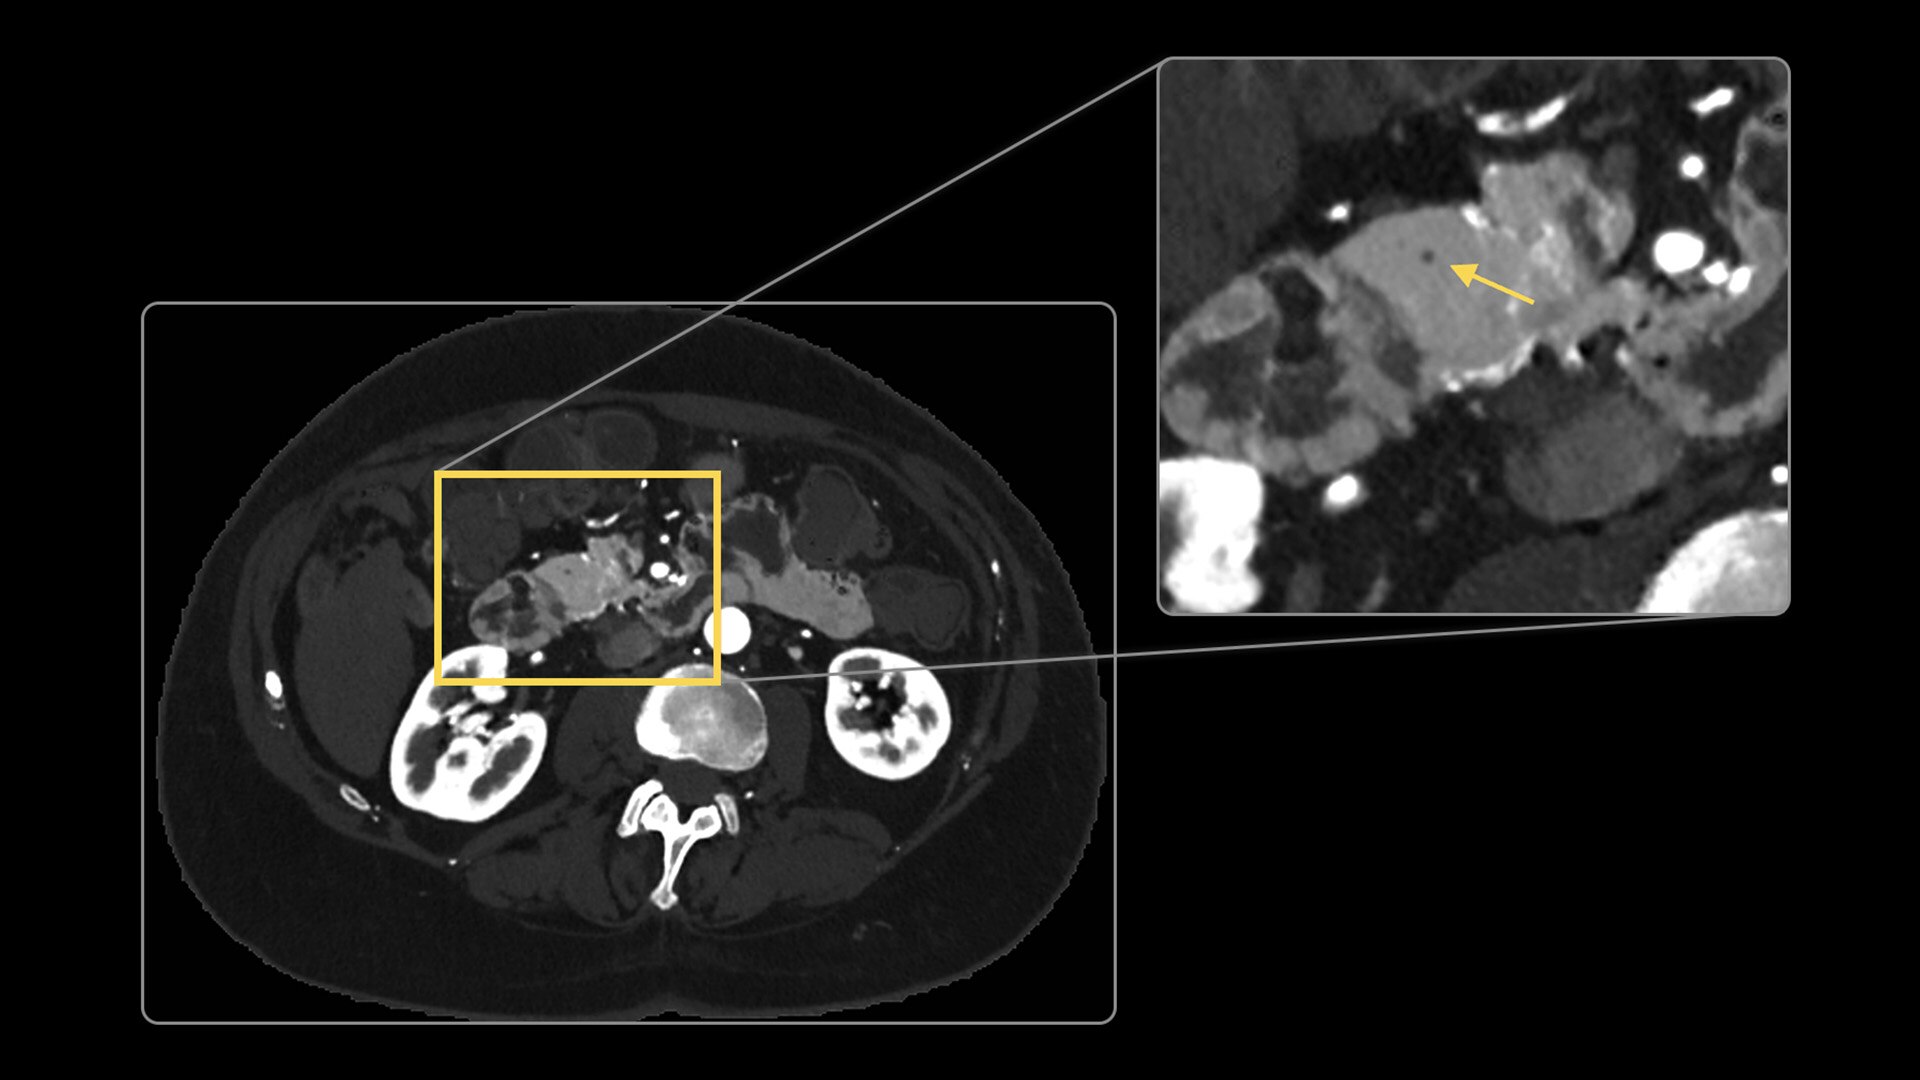

Photonova Spectra provides wide coverage in ultra-high definition imaging with exceptional acquisition speeds, designed to allow you to see your patient’s anatomy in exquisite detail.

With ultra-high spatial resolution scanning capability, Photonova Spectra is designed to help you see incredibly fine details, such as coronary plaque delineation, small microvascular vessels and even tiny structures of the inner ear.

Experience our industry-leading 8 cm detector coverage, combined with up to 0.23 sec rotation speed and ultra-high sampling rates featuring a 50 cm field of view (FOV) in all scan modes. This enables wide-coverage ultra-high definition imaging with reduced organ movement for exceptional image clarity.